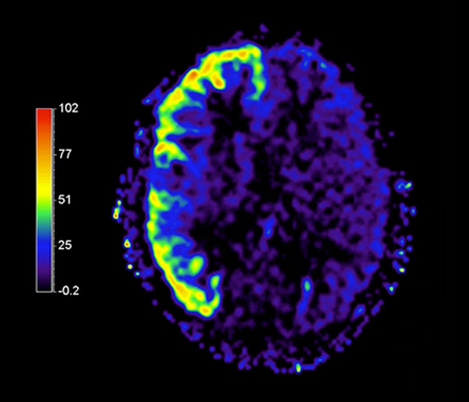

I believe that MRI provides us with a direction towards hypo fractionation, and potentially less toxicity. MR has already become deeply integration into our clinical practice. We have clinical protocols for planning the treatment of virtually all tumor sites like pelvis, brain and esophagus for external beam radiation therapy.

Prof. Dr. M. van Vulpen, Chairman Radiation Oncology Department, Radiation Oncologist, UMC Utrecht, The Netherlands

We’ve worked intensively with Philips for the past 10 years on new developments that make it easier to integrate MRI into our clinical practice. Like dedicated sequences for radiotherapy that give us the high contrast and high geometric fidelity we need for treatment planning.

Dr. C.A.T. van den Berg, MR Physicist, UMC Utrecht, The Netherlands